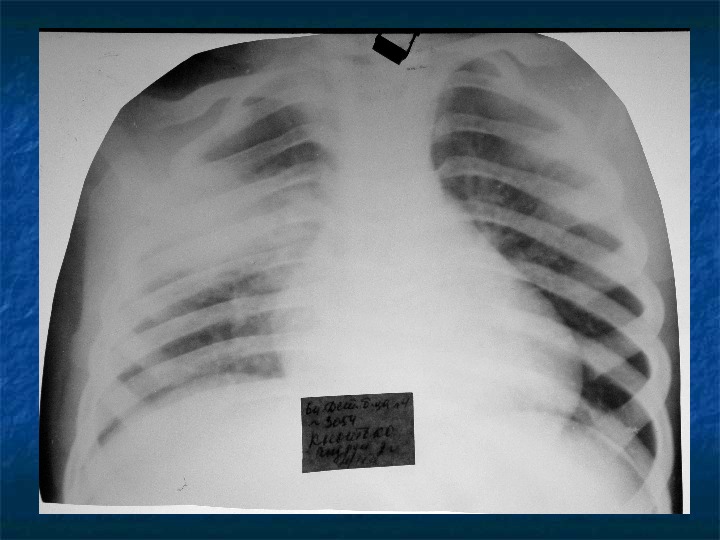

Изучение дозы излучения при рентгеновских исследованиях: визуализация

Раздел: Фотодневник открытий